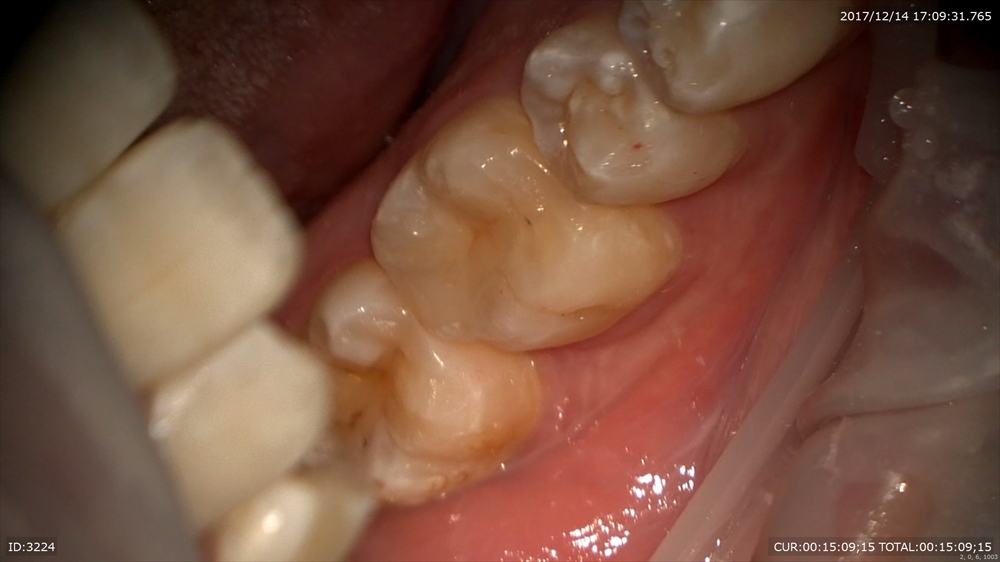

もう1つ虫歯のケース

歯が割れています。マイクロスコープで修復へ。

やはり自然な色が笑った時も美しいですね。